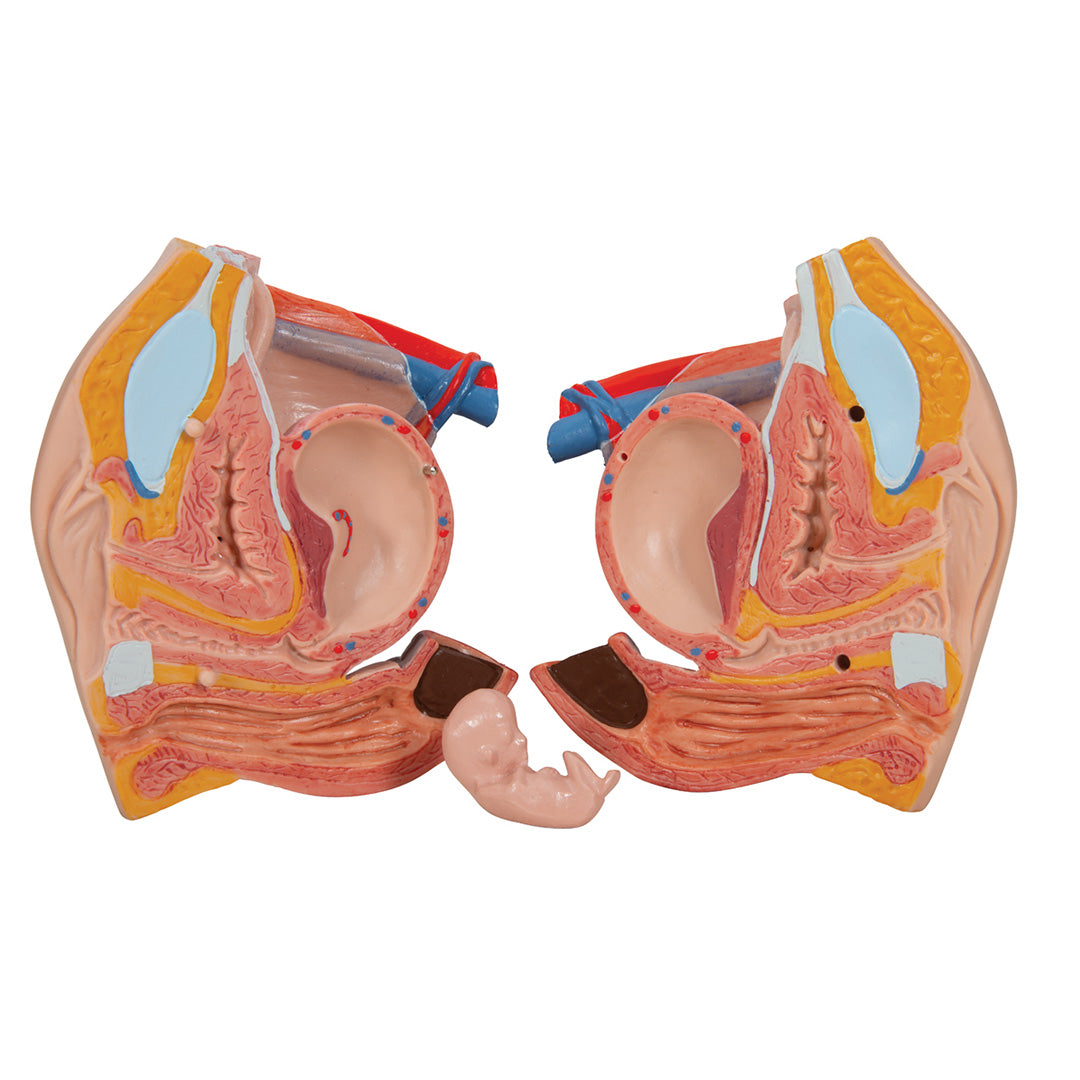

Sobre la anatomía interna humana.

• Órganos genitales femeninos con embrión, en 3 partes